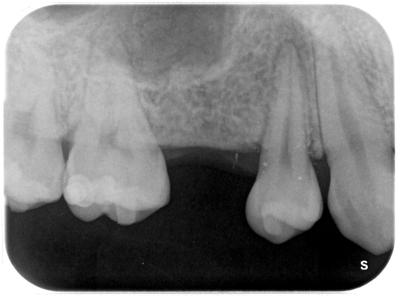

成人後も乳歯が残存し動揺しているが、根本的対応を前医ではできなかった。

術前。

欠損部位に対して、ブリッジ治療もしくはインプラント治療が選択肢となるが、今回、前後の歯牙を削合避けるため、インプラント治療を患者さんは選択された。

上顎洞底が低く、このままではインプラント治療不可能。